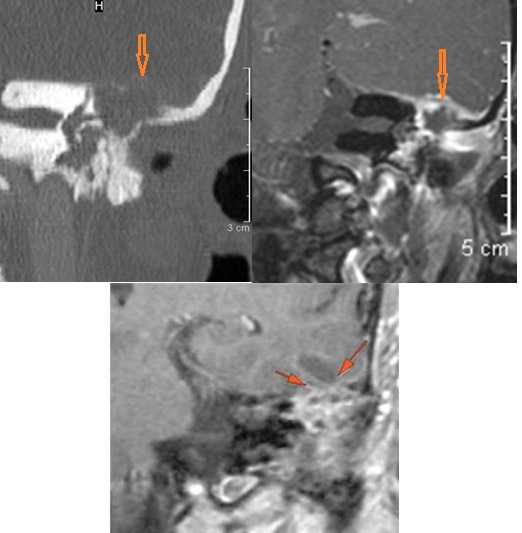

General Skull Base

There are localized, potentially subperiosteal, fluid or pus collection spreading along the petrous apex inferior surface (mainly below the carotid canal) and/or clivus. [Yes/No]

The basisphenoid and basiocciput (clivus) and/or the petrous apex inferior surface (mainly below the carotid canal) is eroded and/or its marrow space infiltrated. [Yes/No]

The floor of the middle cranial fossa is eroded and/or its marrow space infiltrated. [Yes/No]

There is dural reactive change along the floor of the middle cranial fossa or along the inner (intracranial) surfaces of the petrous portion of the temporal bone or clivus. [Yes/No]

There is a subperiosteal, subdural or epidural abscess along the floor of the middle cranial fossa or along the inner (intracranial) surfaces of the petrous portion of the temporal bone or tentorium or falx cerebri. [Yes/No]